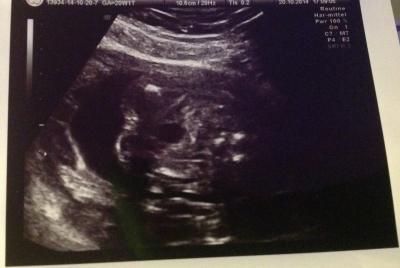

Hallo zusammen, gestern wollte eine Freundin die letzten US-Bilder sehen und bei dem einen fragte sie mich: "Was seh ich hier?" Da ich beim Arzt immer nur auf die Kopfbilder achte, hab ich gar nicht nachgefragt und war gestern auch überfragt. Wisst ihr mehr? Ist das vllt die Outingbestätigung?

Popo von unten, vermutlich das outingbild, dass es ein mädchen wird, also kein Anhängsel zwischen den Beinen hängt

Mädchen ;-)